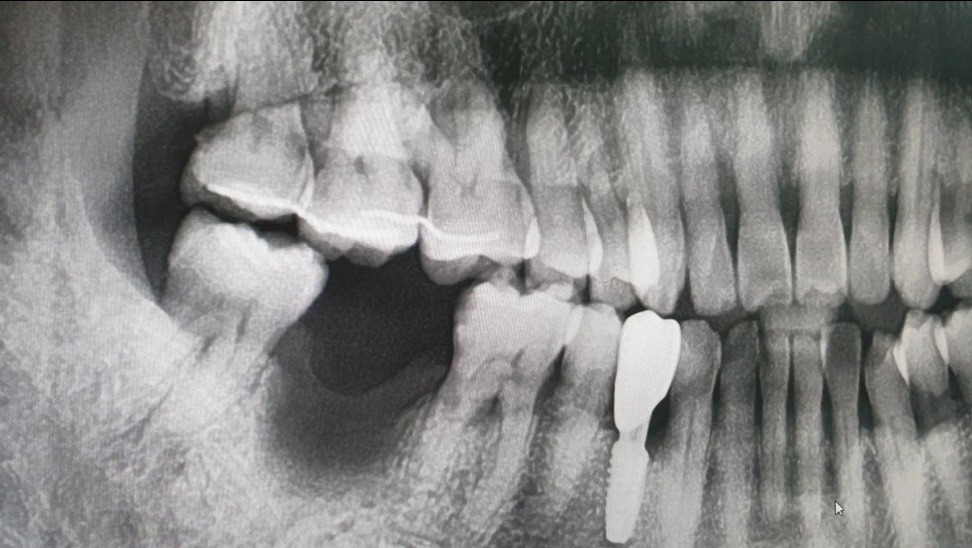

텅빈 우측 아래 어금니의 윗 이빨이 짬짬히 통증이 다가 온다.

강남 치과로 달려가 옛 이빨 사진을 보니 상태가 그때 부터 좋지 않고 이빨 자체도 흔들림이 있다.

공연히 여행중에 또 큰 고통으로 다가 올 것 같아 발치하기로 결정하고 뽑아 보았다.

이빨 빠진 곳에서 썩어 가는 부위가 한가득 나왔다. 이빨도 우쩨 뿌리가 3가닥이나 되는지..